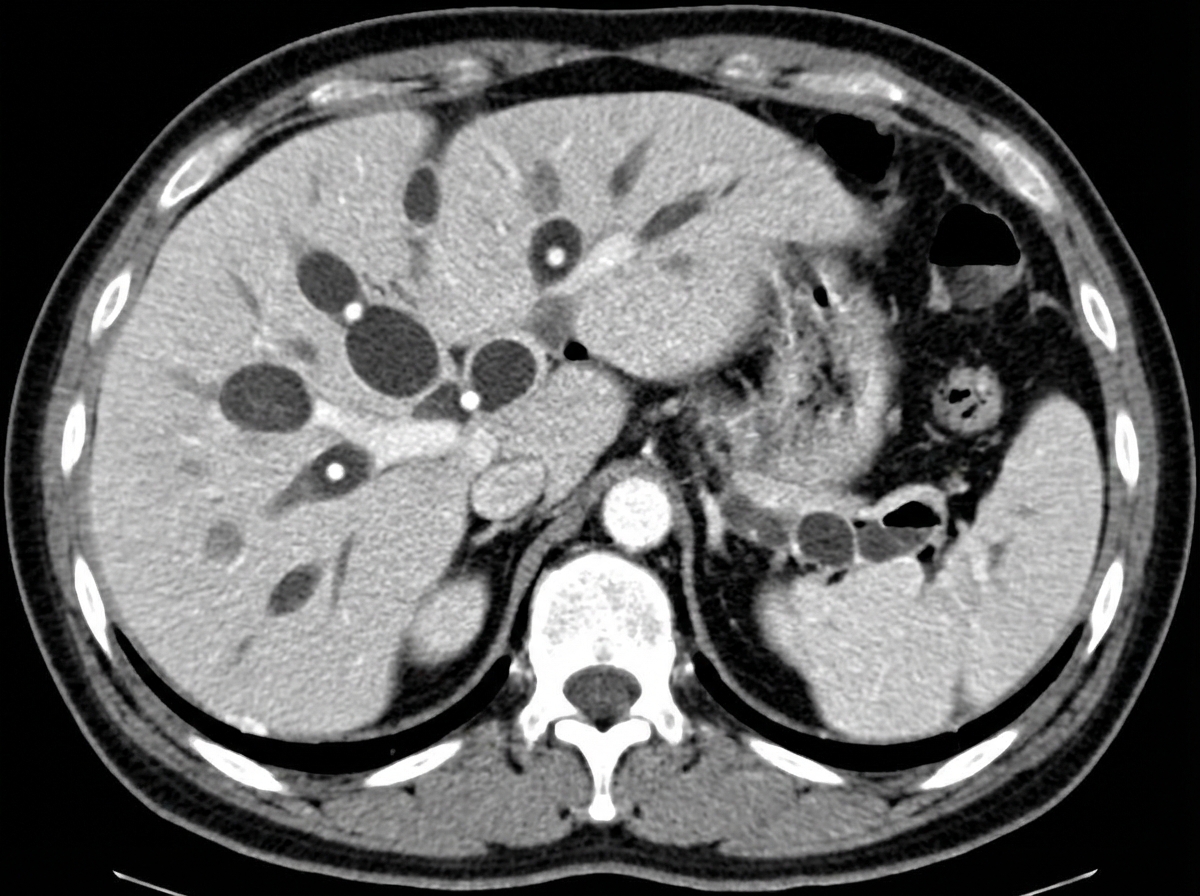

A 10-year-old female presented with recurrent attacks of cholangitis. CECT was done; what is the most likely diagnosis based on CECT findings?

Explanation: ***Type 5 choledochal cyst*** - Recurrent **cholangitis** in a child with **multiple intrahepatic biliary dilatations** on CECT is pathognomonic of **Type 5 choledochal cyst (Caroli disease)**. - CECT shows the characteristic **central dot sign** representing portal vein branches within dilated intrahepatic bile ducts, confirming the diagnosis. *Type 1 choledochal cyst* - Presents as **fusiform dilatation of the common bile duct** with normal intrahepatic ducts on imaging. - Would not show **multiple intrahepatic cystic dilatations** as seen in this case with recurrent cholangitis. *Type 3 choledochal cyst* - Involves **choledochocele** - cystic dilatation of the **distal common bile duct** within the duodenal wall. - CECT would show a **small cystic lesion** in the pancreaticoduodenal region, not intrahepatic changes. *Type 4 choledochal cyst* - Features **both extrahepatic and intrahepatic** bile duct dilatations with **fusiform CBD dilatation**. - Differs from Type 5 as it includes **extrahepatic involvement** and lacks the pure intrahepatic cystic pattern seen here.